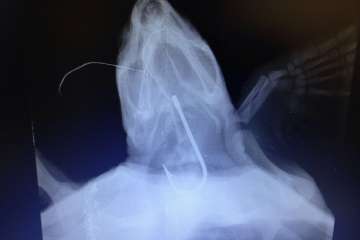

Esta situación se debe a que desde el verano esta planta, ubicada en el tramo bajo del barranco que desemboca en la playa de Hoya del Pozo está absorbiendo al día 1.200 metros cúbicos más de aguas residuales procedentes de los líquidos que le correspondería tratar a la depuradora de Jinámar, que depende del Consejo Insular de Aguas de Gran Canaria.

Con este nuevo caudal adicional, esta estación depuradora ha llegado al límite de capacidad nominal para el que fue diseñada, lo que puede provocar en episodios de lluvia o imprevistos que sea incapaz de tratar todos los caudales y que, por tanto, se produzcan vertidos de aguas no depuradas por medio de su emisario.